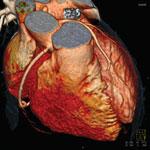

Trends and new technology for cardiac computed tomography angiography (CCTA) were highlighted during the 2012 Society of ...

There are currently three major trends in cardiovascular computed tomography (CT) technology — lowering radiation dose ...

As catheter-based, minimally invasive procedures expand rapidly beyond treatment of the coronary arteries into all areas ...